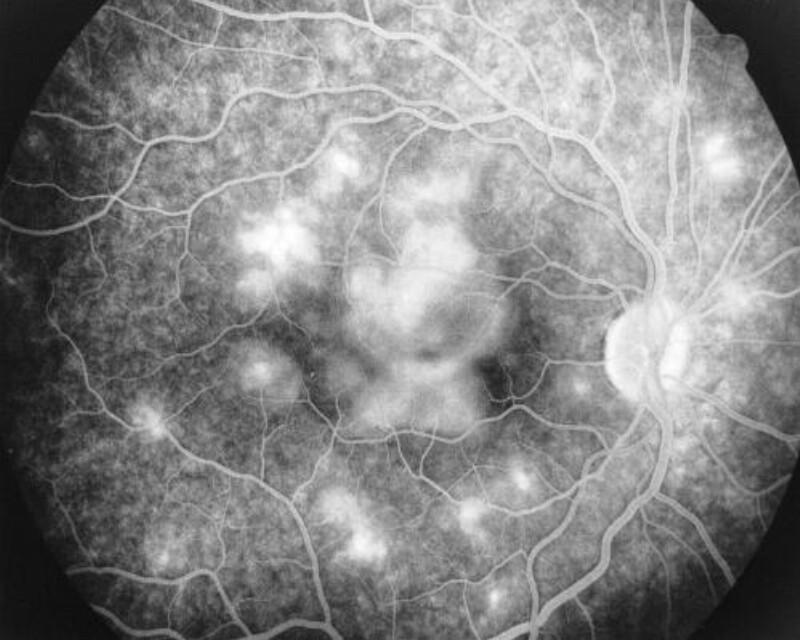

épithélite aigue